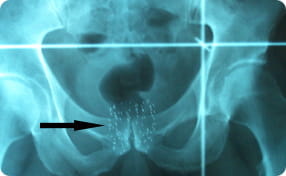

Brachytherapy, or prostate seed implantation, is a type of radiation therapy in which radioactive metallic seeds — smaller than a grain of rice — are permanently placed inside the prostate gland.

The seeds give off their radiation slowly over several months and, within one year, their radiation completely decays. The seeds can remain safely in place for the rest of a man’s life.

It will include x-rays and a CT scan of the pelvis to indicate the positioning of the seeds and help determine the dose of radiation the prostate is receiving.